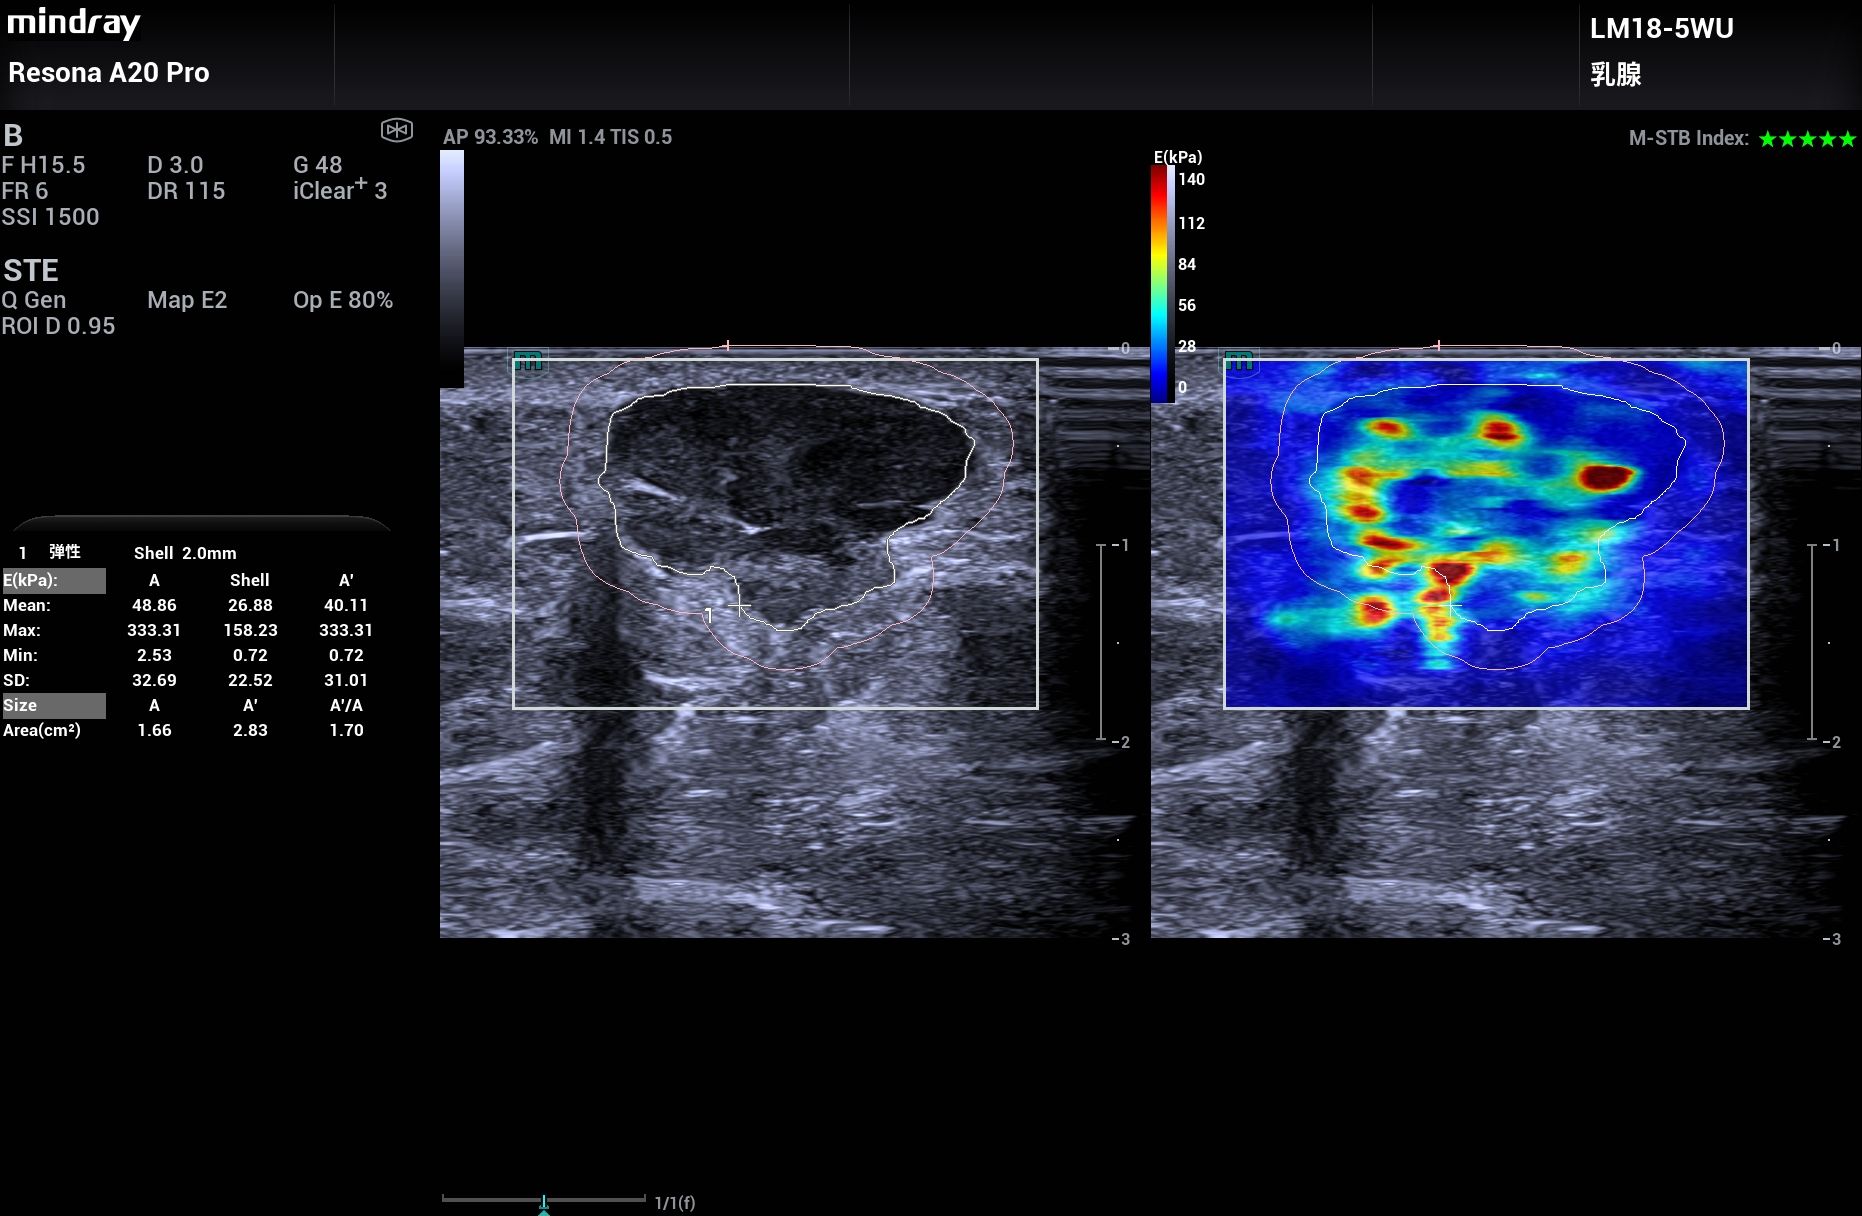

采用A20的超微血流UMA、睿瞳技术、弹性成像、造影和造影分析等高级技术。

其中睿瞳技术可以观察肿瘤周围边界的炎症高回声表现。

让乳腺疾病诊断更可信赖,更加精准。2025年11月。